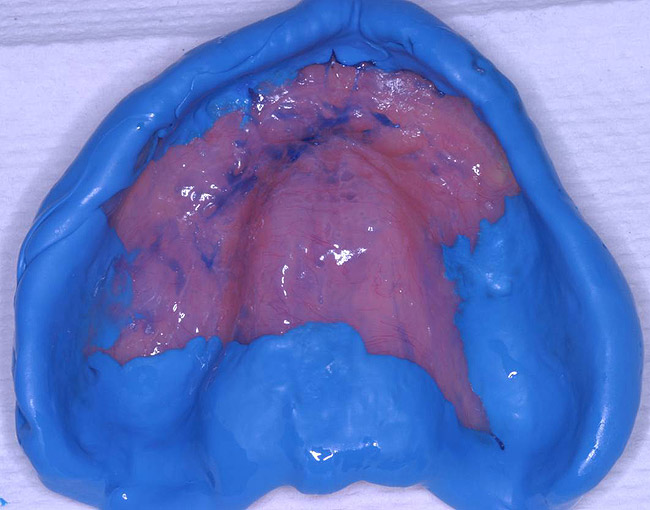

Figure 3  Occlusal view of AlgiNot impression of existing lower denture to be poured up in stone.

Figure 3

While the patient was viewing the CAESY Education Systems (Vancouver, WA) denture module on DVD in the operatory for consent and educational purposes, the mandibular denture was taken from the patient and impressed using an alginate alternative with an automix delivery system (AlgiNot, Kerr Corporation, Orange,CA) (Figure 2). After the 2-minute, 45-second set time recommended by the manufacturer, the denture was removed from the impression to reveal an accurate replica of the lower denture (Figure 3). The mandibular denture impression was disinfected with antimicrobial spray and walked to the dental laboratory, where it was poured up with yellow stone (Denstone® Golden, Heraeus Kulzer, Armonk, NY) by the laboratory technician to provide an occlusal reference and opposing model for the maxillary prosthesis. The lower denture was given back to the patient at this point in time and she was informed verbally of the next stepsin the procedure involving the use of her existing upper denture as a custom impression tray (Figure 4).